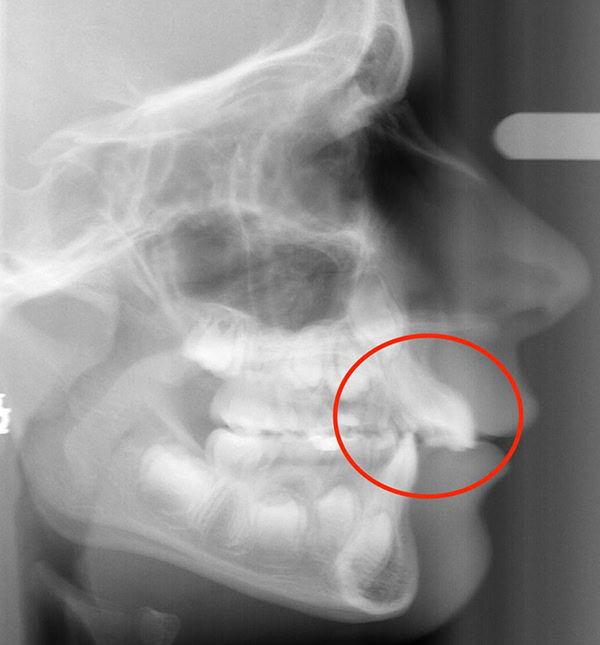

Actual Patient: Alexander

Alexander Before 4 Alexander After 4

Severe “Underbite”, Narrow Jaws, Adult Teeth Not Growing In

Alexander Before 1 Alexander After 1

Front View

Top View

Right & Left Sides